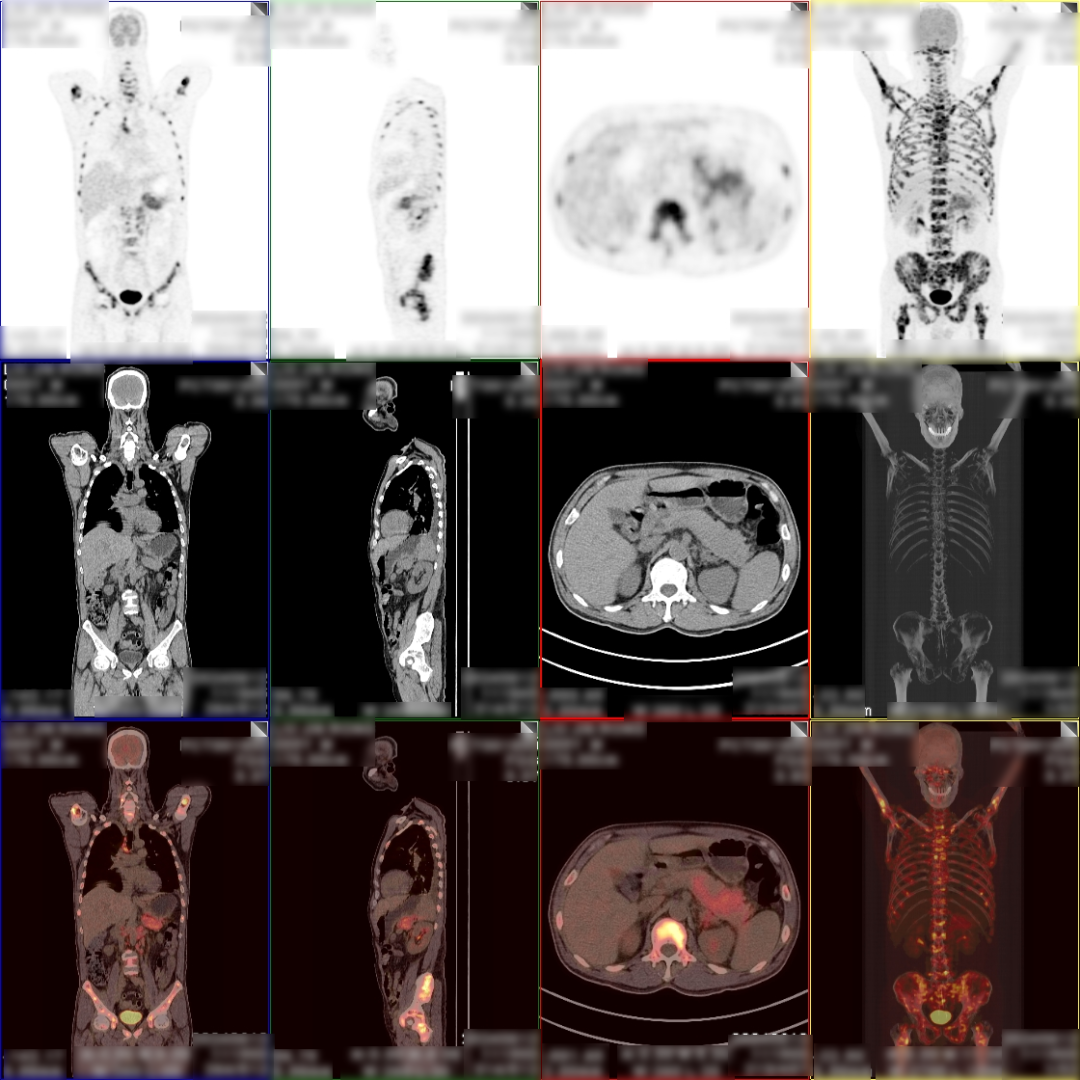

病史:男,55岁,腹痛伴乏力3天入院检查,MR:胰尾部肿物,考虑胰腺癌并多发淋巴结转移;超声胃镜下胰腺活检未见癌细胞,为了解全身状况申请PET检查。

PET/CT检查所见

空腹 6h 以上,静脉注射显像剂 18F-FDG,平静休息 60min 后行全身 PET 及 CT 断 层显像,解剖与功能图像行多层面、多幅显示,影像清晰。

PET/CT诊断意见:

1、胰腺体尾部块状胰腺癌,病灶侵犯相邻胃体部胃壁,并可能侵犯左侧肾周筋膜,肿块远端胰尾部胰管扩张;盆腔少量积液;

2、胰腺尾部周围、中上腹部腹膜后区腹主动脉周围及纵隔内(1R、1L、2R、4R、5、7 组)多发淋巴结转移灶;

3、双侧尺骨近端、双侧肱骨、右侧颞骨、枕骨、蝶骨、双侧下颌骨头、双侧锁骨、双侧肩胛骨、胸骨、脊柱各椎体、双侧各肋骨、骨盆诸组成骨、右侧股骨头、双侧股骨颈及股骨干广泛骨转移灶,其中左侧第 2、4 前肋、右侧第 4、7 侧肋病理性骨折。

PET/CT活检病理:胰腺癌